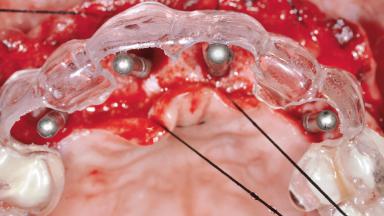

Replacement of Six Teeth with a Fixed Dental Prosthesis on Four Bone-Level Implants